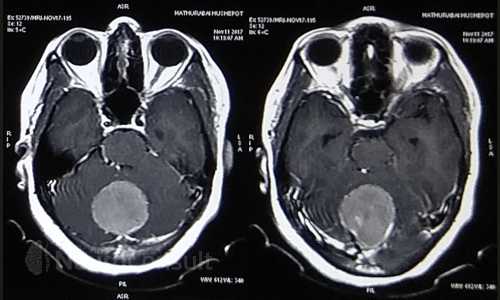

My Cases Studies & Work